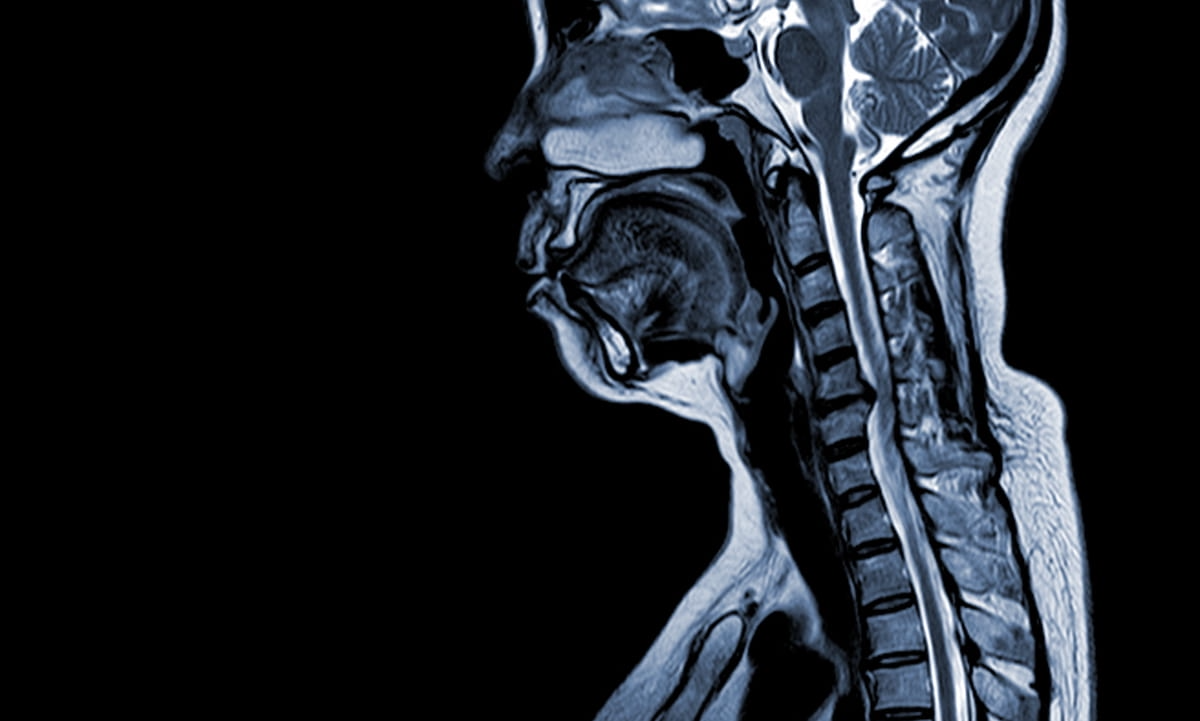

FIRMM-pix, a brain magnetic resonance imaging (MRI) software module recently launched at the International Society for Magnetic Resonance in Medicine (ISMRM) conference, reportedly employs visual biofeedback and gamification that coaches patients to stay still during brain MRI exams.